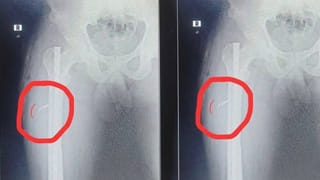

ఈ దాడిలో ఆ యువకుడికి తొడలకు గాయాలయ్యాయి. వెంటనే ప్రభుత్వం ఆస్పత్రికి తరలించారు. బాధితుడు తెలిపిన వివరాల మేరకు గూడెం సమీపంలోని అటవీ ప్రాంతంలోకి కట్టెలు తెచ్చుకునేందుకు వెళ్లగా ఎలుగుబంటి దాడిచేసి తొడను గాయపరిచిందన్నాడు. గట్టిగా అరుస్తూ పారిపోతుండగా మరో 2 ఎలుగుబంట్లు దాడి చేసేందుకు ప్రయత్నించాయన్నాడు. బాధితుడిని సున్నిపెంట ప్రభుత్వ వైద్యశాలకు తరలించి చికిత్స అందిస్తున్నారు. ప్రభుత్వ వైద్యశాలలో చికిత్స పొందుతున్న గిరిజన యువకుడు చిన్న దేవయ్యను అటవీ శాఖ అధికారులు పరామర్శించారు. అడవిలో ఒంటరిగా వెళ్లే ప్రజలు అప్రమత్తంగా ఉండాలని అటవీశాఖ అధికారుల హెచ్చరించారు.